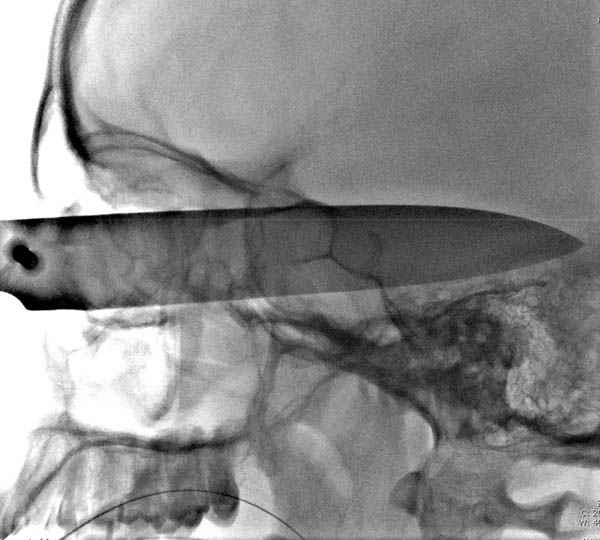

В своих выступлениях я рассказывал, что наши центры в мирное время по пенетрирующим травмам не уступает Ираку или Афганстану, и вот недавно к нам поступила больная 22 лет, травма "ножом в глаз" от бывшей подруги нынешнего "бой френда".

При поступлении в сознании, жаловалась на неприятные ощущения в глазнице.

По протоколу сделаны все необходимые исследования: рентген, ангиограмма с 3Д реконструкцией, где обнаружили что все жизненно важные сосуды не задеты, даже некоторые "сидят" изгибаясь на ноже.